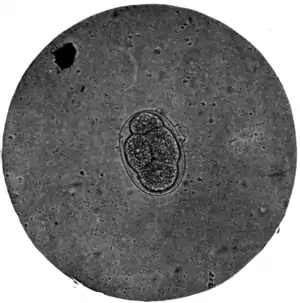

Fig. 173.—Ovum of A. duodenale, x 250. (Photograph by Dr. J. Bell.)